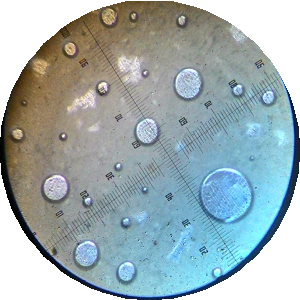

Average globular diameter test

The average globular diameter was measured by the polarizing microscope, which equipped with a calibrated ocular lens and micrometre. The double emulsion was placed on the object glass and covered with glass. Then it was observed using a microscope at 200 times magnification. The observed images were photographed and measured the globule diameter. The average globule diameter test was performed at weeks 0 and 4 [18].

The measurement of the average globular diameter was to see the droplet stability of a double emulsion of snakehead fish powder as shown in table 5 which performed on the external and internal globules using a microscope with a micrometer at 200 times magnification.

| 4 | 8.90±2.45 | 6.01±0.57 | 6.35±1.76 | 4.72±2.57 |

According to Fatimah stated that oil-in-water emulsions (secondary) can be formed when using surfactants with high HLB values such as Tween 80 (HLB 15). Meanwhile, in her study comparing the use of Tween 80 with a concentration of 0.5%, 1% and 1.5% w/v, it was found that the use of Tween 80 at a concentration of 0.5% and 1% had not been able to form an o/w type emulsion (secondary). While at the concentration of 1.5% formed emulsion type o/w (secondary) with the size of globular diameter 1-5 μm. This is related to the obtained results, which indicates that the higher Tween 80 concentration used (F4) in the o/w type secondary emotion, the greater average globular diameter as shown in fig. 5. However, the average globular diameter decreased during the week 4. This corresponds to the double emulsion instability of coalescence between the inner and outer liquid phases marked by a decrease in the average size of the globular diameter of formula [16].

A B

C D

Fig. 5: The picture of globular diameter each formula the week 4, (A): a droplet of F1; (B): F2; (C): F3; (D): F4